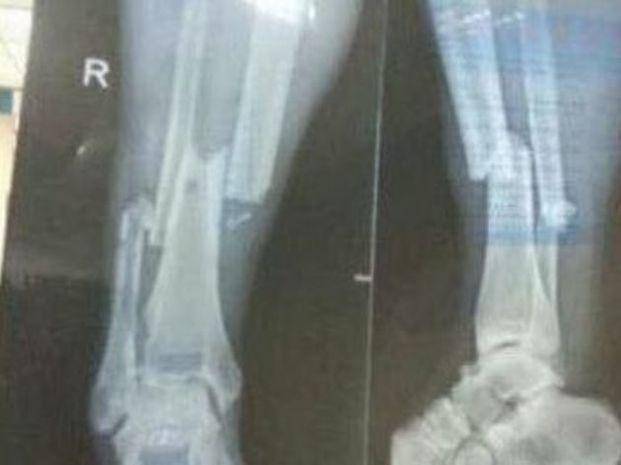

El francés Demba Ba sufrió una dura lesión y las imágenes del momento en que la sufre son impactantes, al igual que la radiografía que luego le practicaron para constatar que el futbolista del Shanghai Shenhua habia sufrido una fractura en la zona de la tibia y el peroné

En tanto, se estima que al jugador, de 30 años, le esperan mínimo ocho meses de recuperación, más una larga e intensa recuperación para volver a jugar.